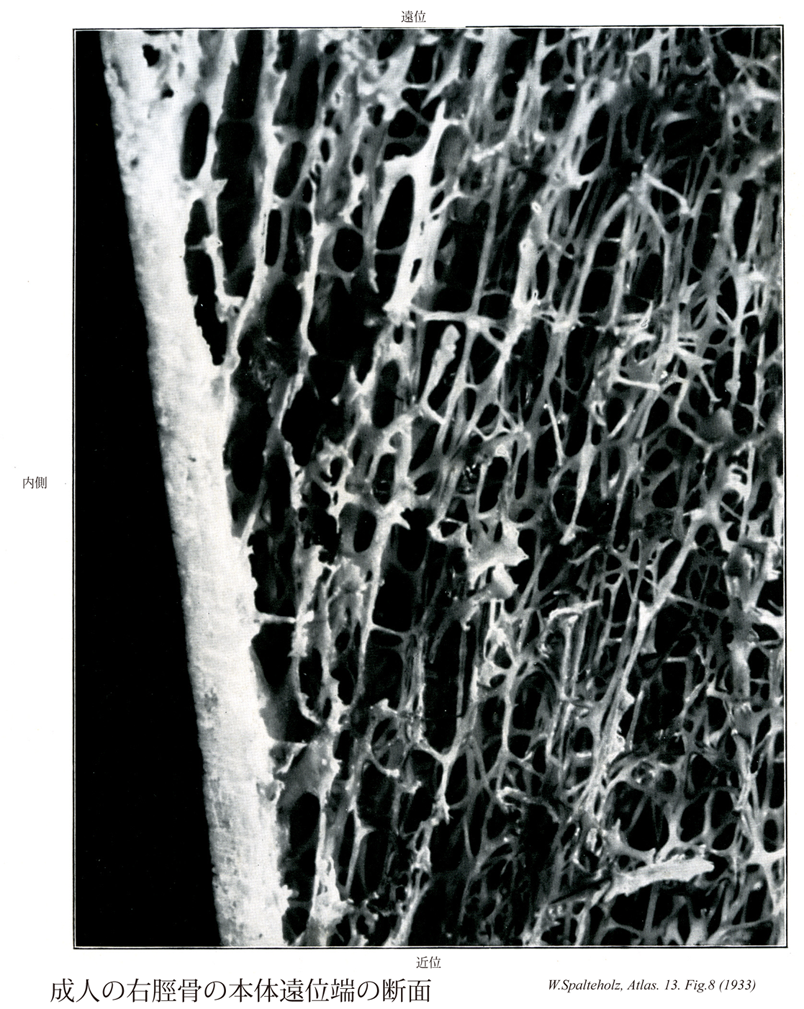

008